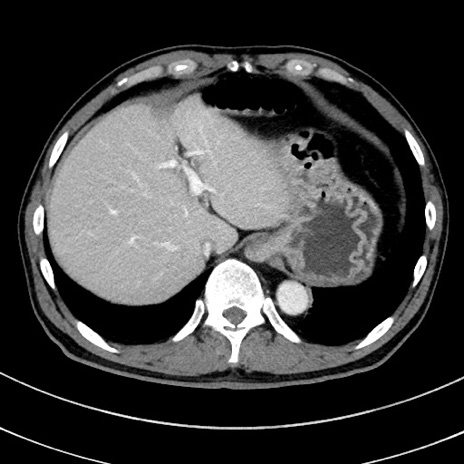

冠状断像

【症例】 60歳代男性

【主訴】 黒色吐物

【現病歴】 4日前から嘔気自覚、2日前の朝食後にも嘔気あり、自分で手で嘔吐反射起こし嘔吐したところ血が混ざっていたため受診。

【既往歴】 5年前汎発性腹膜炎を伴う急性虫垂炎で手術、高血圧、前立腺肥大症、高脂血症

【身体所見】 腹部正中に手術癩痕あり 腹部平坦・軟圧痛なし膨満感あり

【データ】WBC 8400、CRP 4.54